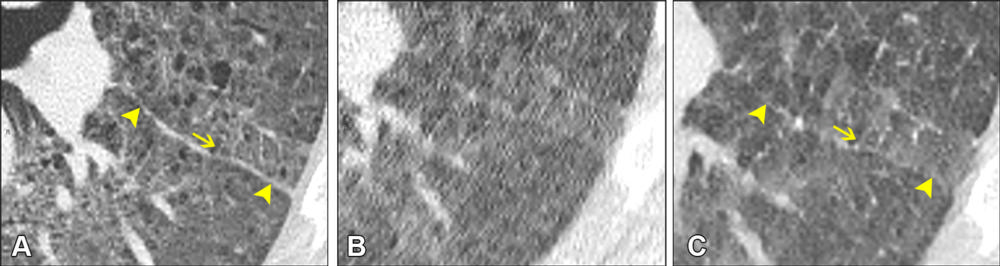

Figure 1. Axial noncontrast chest CT lung window images of three different sample patches shown in each row. Ultra-low-dose [ULD] patches before alignment (left column) are clearly misaligned to the normal-dose patches (middle column). After alignment (right column), the spatial misalignment is mostly compensated.